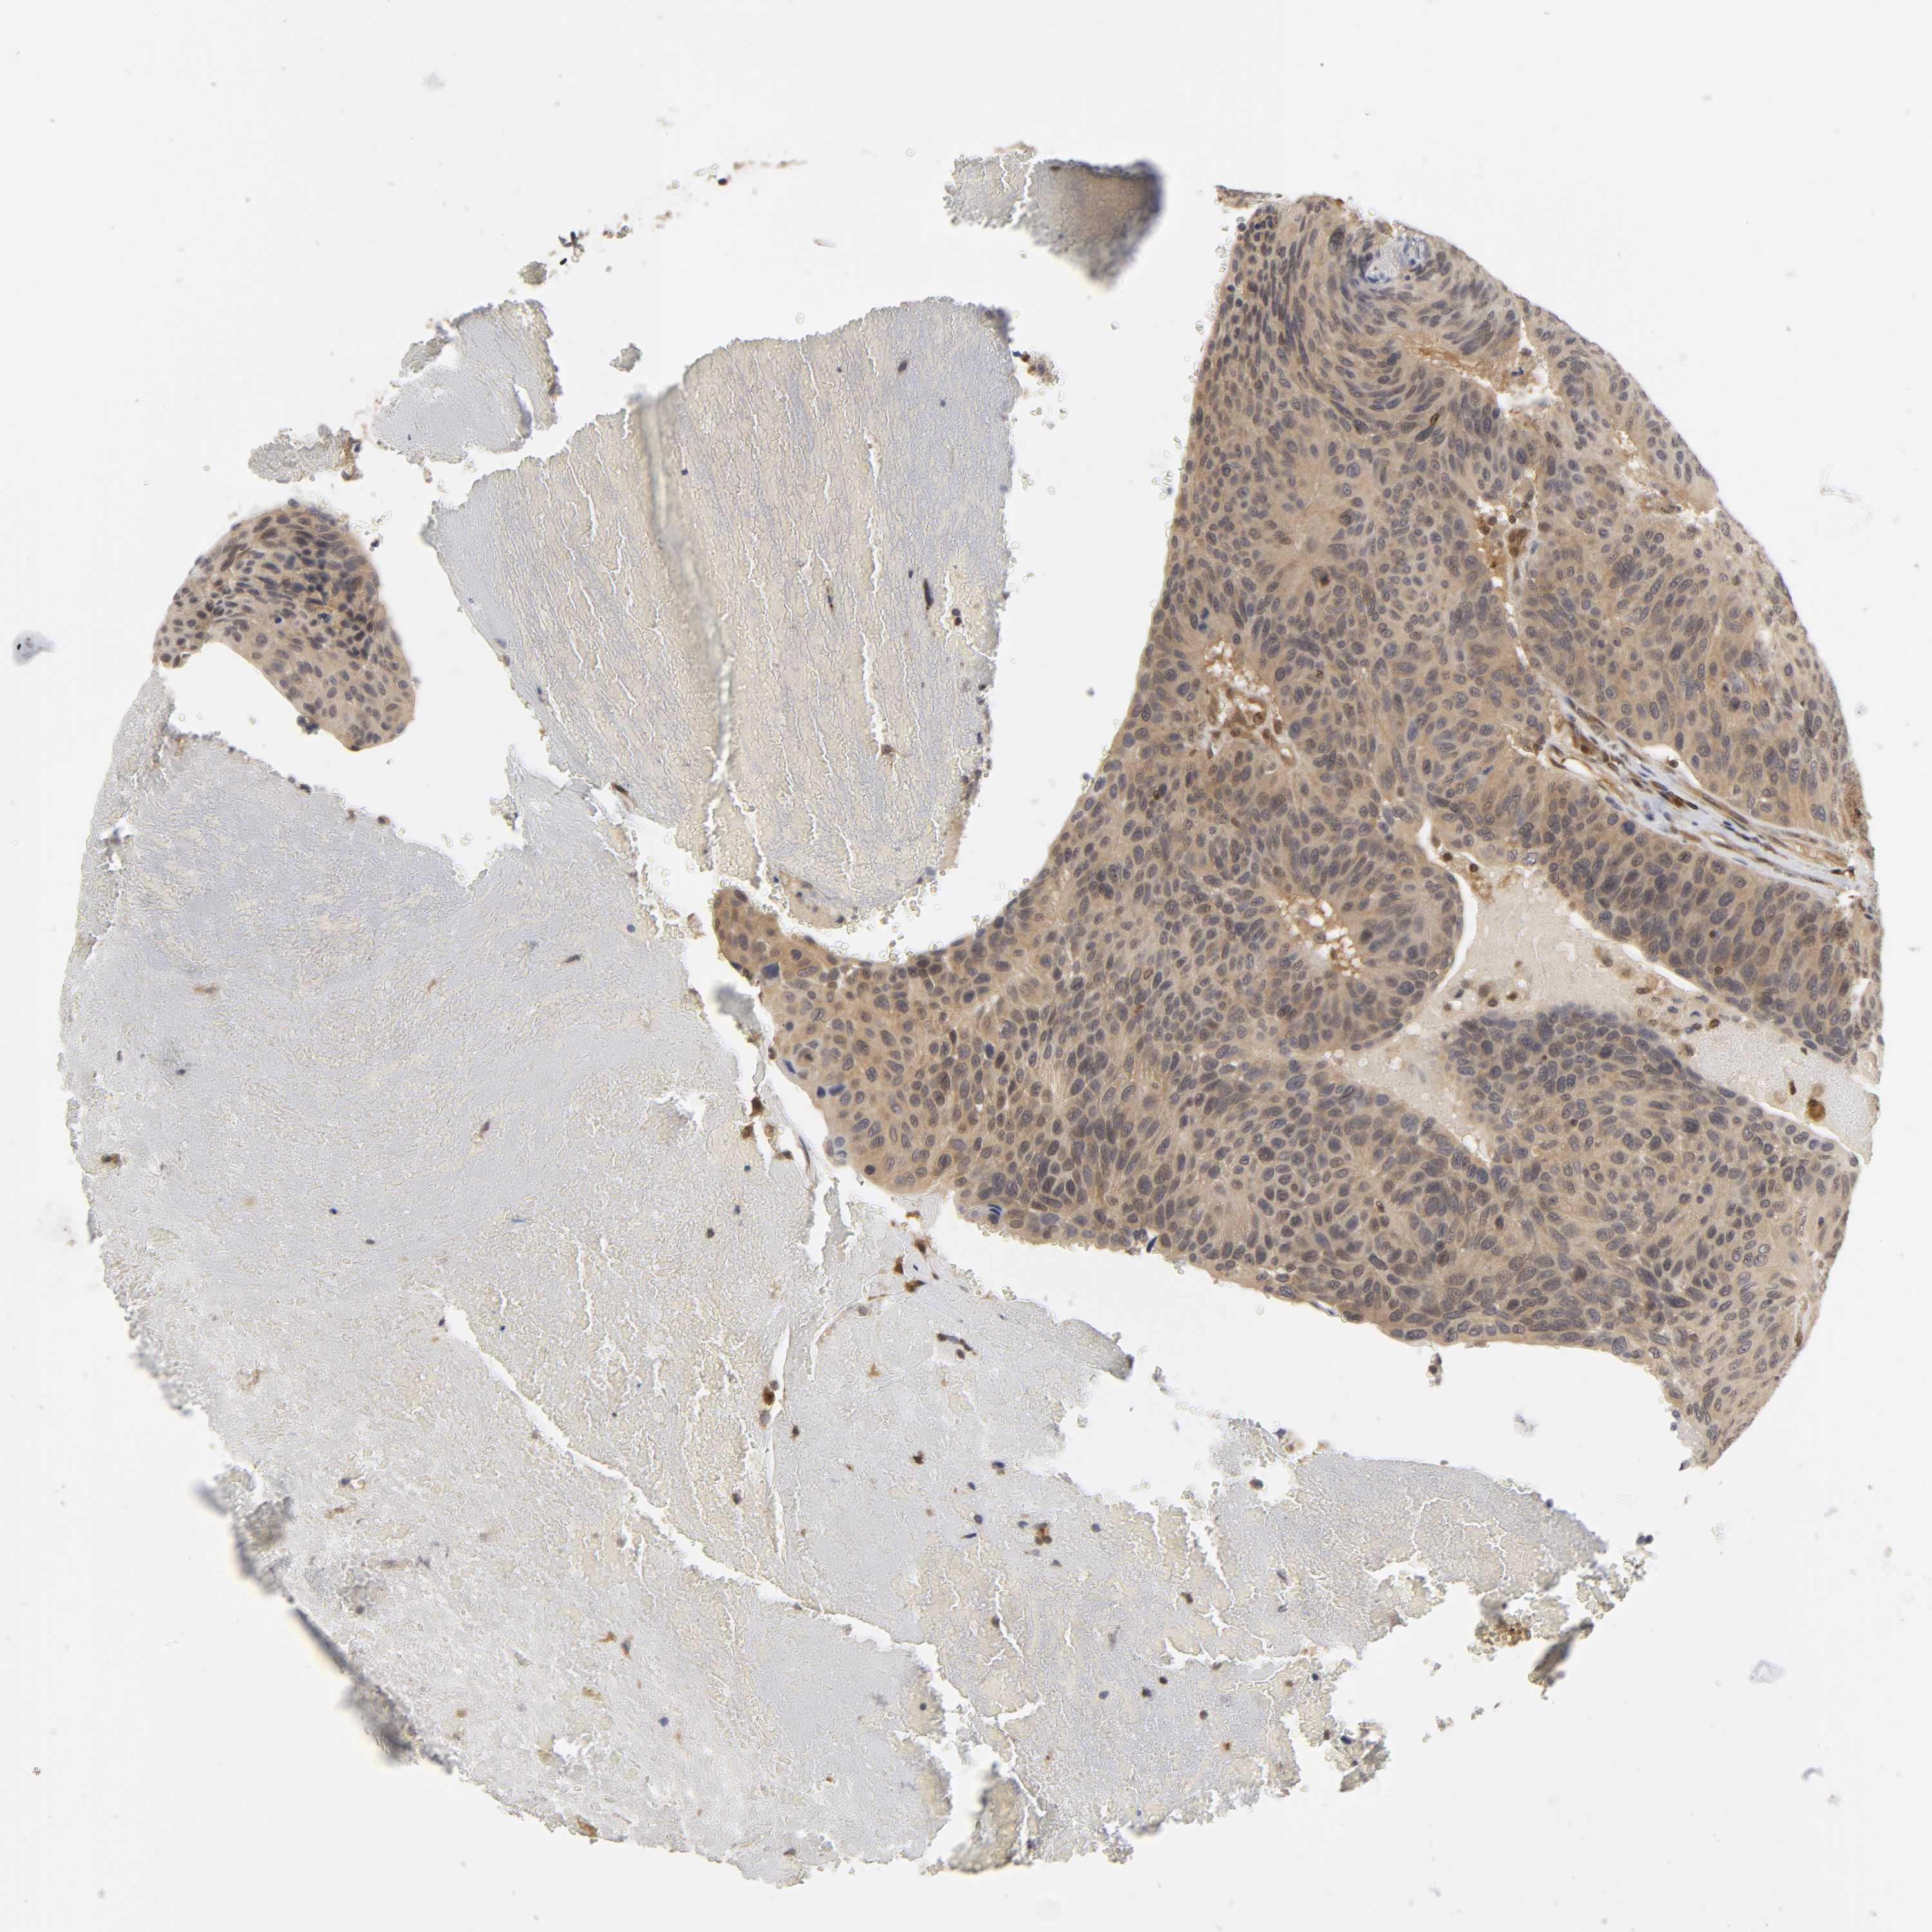

UROTHELIAL CANCER - Protein expressioni

A mouse-over function shows sample information and annotation data. Click on an image to view it in a full screen mode. Samples can be filtered based on level of antibody staining by selecting one or several of the following categories: high, medium, low and not detected. The assay and annotation is described here.

Note that samples used for immunohistochemistry by the Human Protein Atlas do not correspond to samples in the TCGA dataset.

Antibody stainingi

Antibody staining in the annotated cell types in the current human tissue is reported as not detected, low, medium, or high, based on conventional immunohistochemistry profiling in selected tissues. This score is based on the combination of the staining intensity and fraction of stained cells.

Each image is clickable and will lead to virtual microscopy that enables deeper exploration of all samples and also displays staining intensity scores, fraction scores and subcellular localization as well as patient and tissue information for each sample.

Antibody HPA004190

Antibody CAB005870

Staining

High

Medium

Low

Not detected

Intensity

Strong

Moderate

Weak

Negative

Quantity

>75%

75%-25%

<25%

None

Location

Nuclear

Cytoplasmic/membranous

Cytoplasmic/membranous,nuclear

Urothelial carcinoma, High grade

Urothelial carcinoma, Low grade